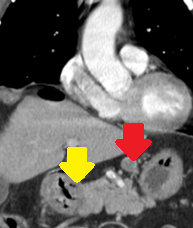

Yellow arrow — Thick-walled gallbladder with gallstones. Blue arrow — Stomach segment. Light blue arrows — Cholecystogastric fistula (Courtesy Dr. V. Penopoulos)